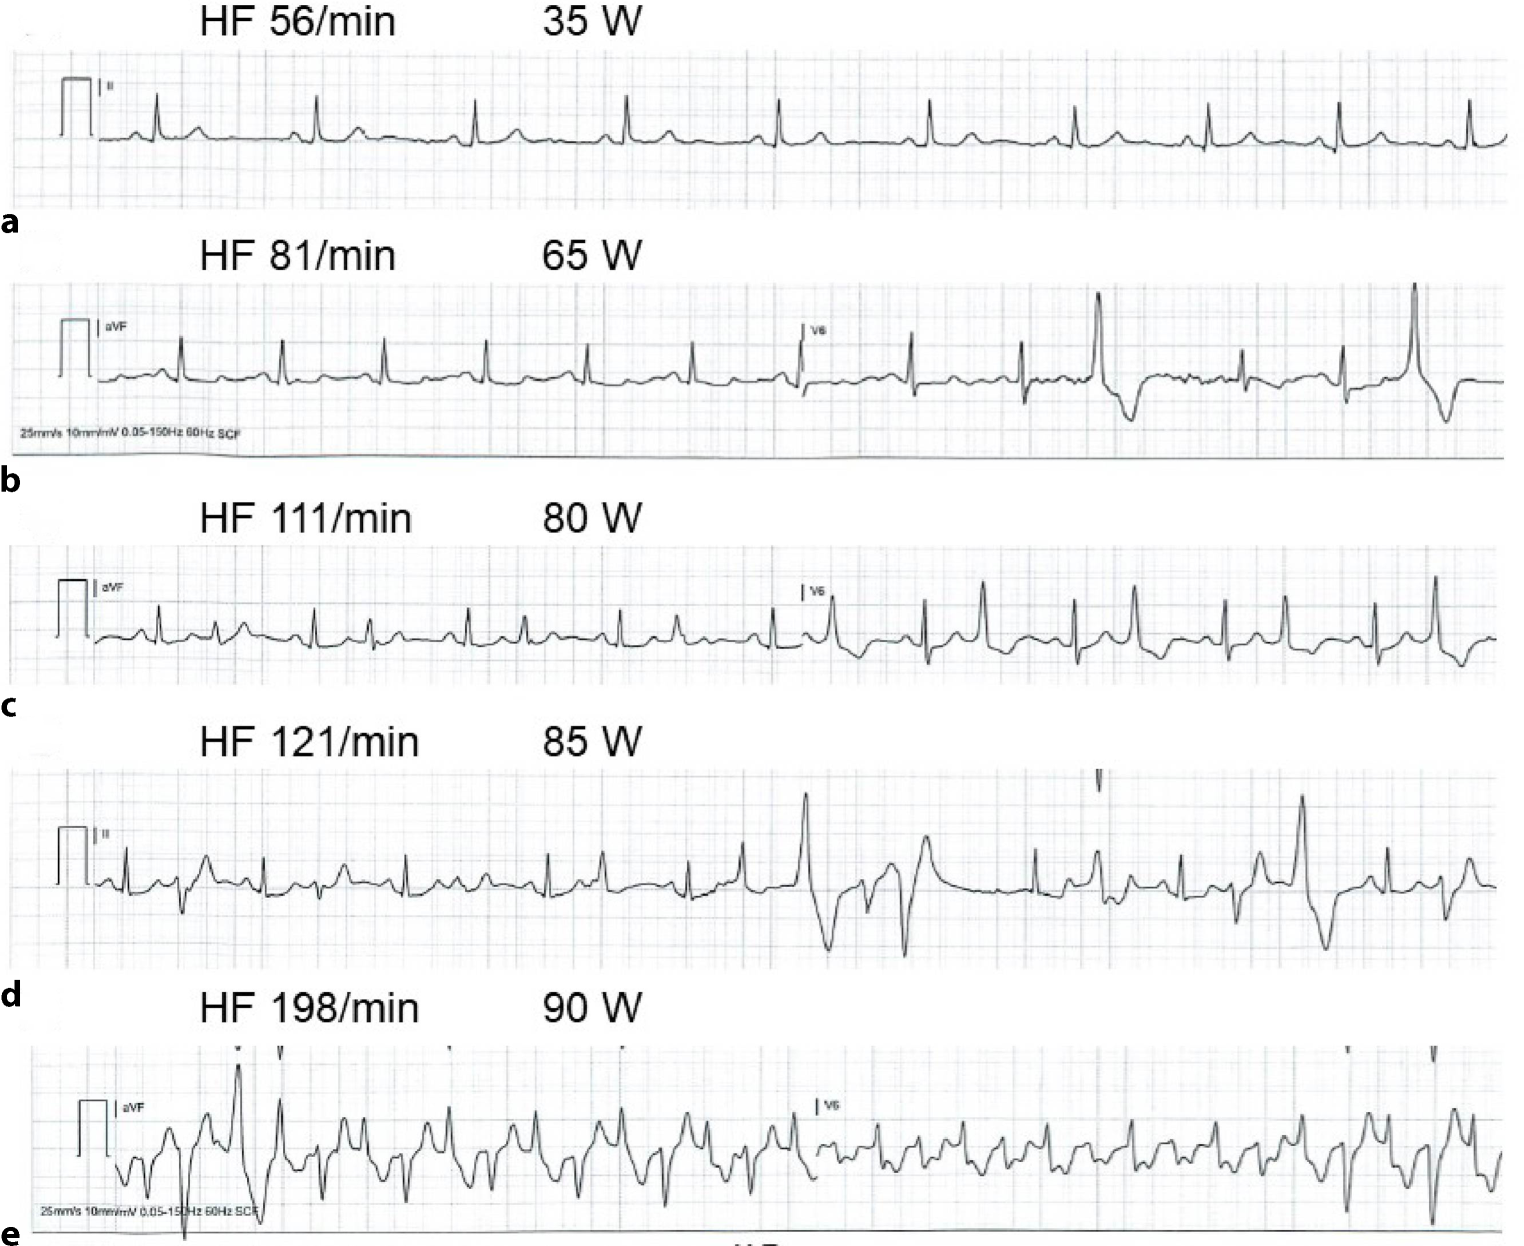

CPVT is characterised by stress-induced polymorphic and bidirectional ventricular arrhythmias (Fig. 2). The diagnosis is made when exercise stress testing (EST) unmasks the arrhythmic phenotype but cardiac imaging reveals no evidence of structural heart disease [5]. Most cases are caused by variants in RYR2, a gene that codes for the component proteins of the large homotetrameric cardiac ryanodine receptor, which controls calcium release from the sarcoplasmic reticulum.

Exercise stress test of patient with catecholaminergic polymorphic ventricular tachycardia showing ventricular arrhythmia that increased in severity as workload attenuated and resolved after cessation of exercise. a Normal sinus rhythm without premature ventricular complexes (PVCs), b isolated PVCs, c PVCs in bigeminy, d polymorphic couplet and triplet following PVCs in bigeminy, and e typical bidirectional ventricular tachycardia at peak exercise. HF heart frequency